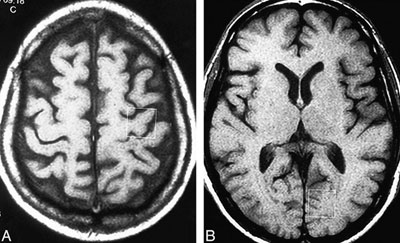

هیچ آزمایش درست و درمانی وجود ندارد که علائم ALS را تایید کند. پزشک شما این بیماری را بر اساس آزمایش در یک فرآیند حذف گزینه‌های احتمالی تشخیص خواهد داد؛ زیرا بخشی از علائم این بیماری با برخی بیماری‌های دیگر عصبی مشترک است. برای انجام این کار و رسیدن به نتیجه نهایی در تشخیص بیماری، گاهی لازم است برخی روش‌های معاینه و نیز آزمایش‌هایی دیگر به کار گرفته شود.

رایج‌ترین این روش‌ها عبارتند از:

ـ اسکن MRI